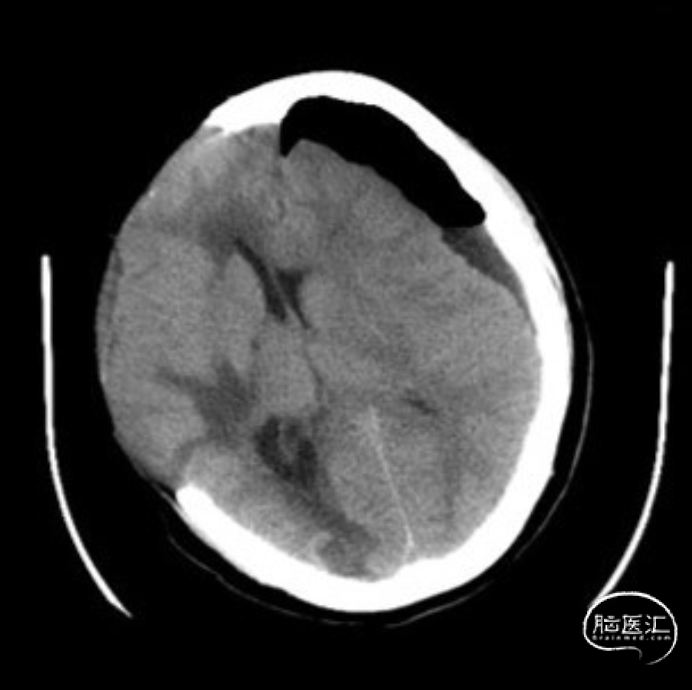

入院头颅CT:右侧颅骨缺失,左侧硬膜下积液,中线右偏明显。